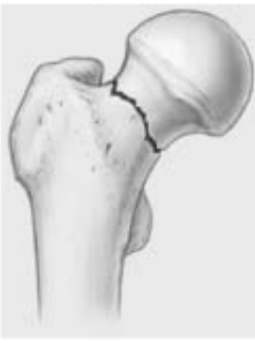

Quel type de fx de la hanche suis-je?

A

col fémoral

Vascularisation de la tête fémorale interrompue –> NÉCROSE AVASCULAIRE

Tx prothèse hanche seulement pour ce type de fx = permet pt de marcher + rapidement